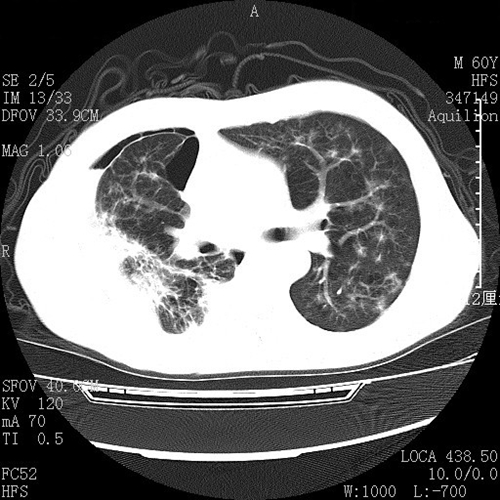

肺腺癌圖片

浸潤性肺腺癌早期症狀

肺腺癌腫瘤

肺腺癌左肺全切